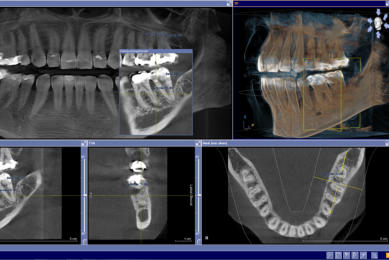

Für den Zahnarzt haben Röntgenaufnahmen einen unverzichtbaren Stellenwert in der Diagnostik und Behandlungsplanung. Für die Implantologie und viele andere zahnärztliche Bereiche bietet das digitale Röntgen eine optimale Möglichkeit der Vorplanung und Unterstützung während der Behandlung. Digitale 2D-Röntgenbilder und DVT´s/ 3D-Röntgenbilder können wir in besonders hoher digitaler Qualität und geringer Strahlendosis durchführen.

sehr hohe Auflösung und Kontrast sehr geringe Strahlenbelastung sofortige Bilddarstellung in Echtzeit optimale Vergrößerungsmöglichkeiten umfangreiche Bildnachbearbeitung punktgenaue Vermessung von Strecken gemeinsame Ergebnisauswertung mit dem Patienten Hochauflösende Panoramaaufnahme:

3D- Röntgen - DVT